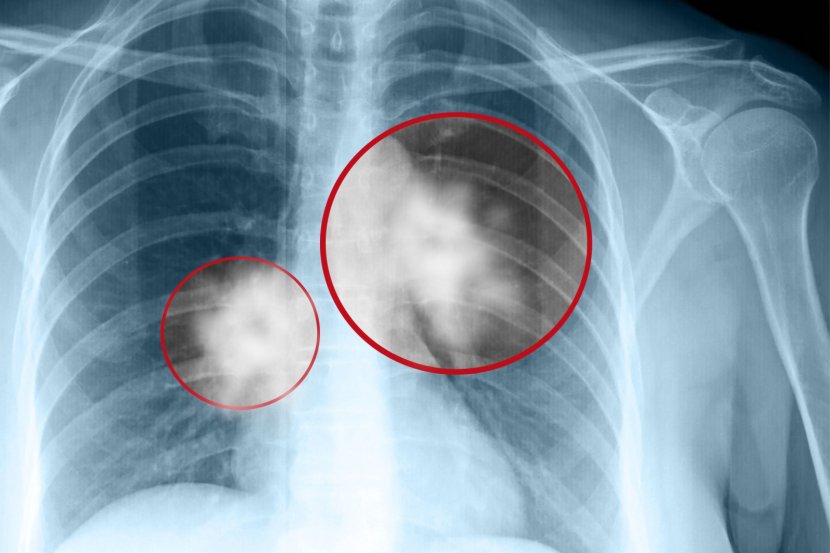

Osobe koje su dobile karcinom pluća, a nikada ranije nisu pušile obično imaju veću učestalost mutacija koje imaju veze sa razvojem raka pluća

Rak pluća, koji se uglavnom dovodi u vezu sa muškarcima i osobama koje puše, sada se češće dijagnostikuje kod žena mlađih i srednjih godina, pokazuju rezultati novog istraživanja. Studija, objavljena prošle nedelje u JAMA Oncology, otkrila je da su stope novodijagnostikovanih slučajeva raka pluća bile veće kod žena starosti od 35 do 54 godine nego kod muškaraca istog uzrasta – uprkos opštem trendu pada stope incidencije raka pluća.